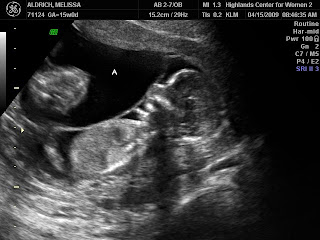

to looking like sweet babies!

The miracles of God knitting little ones in my womb is just incredible to watch by ultrasound!

Do you think they’ll be identical or not based on these photos?